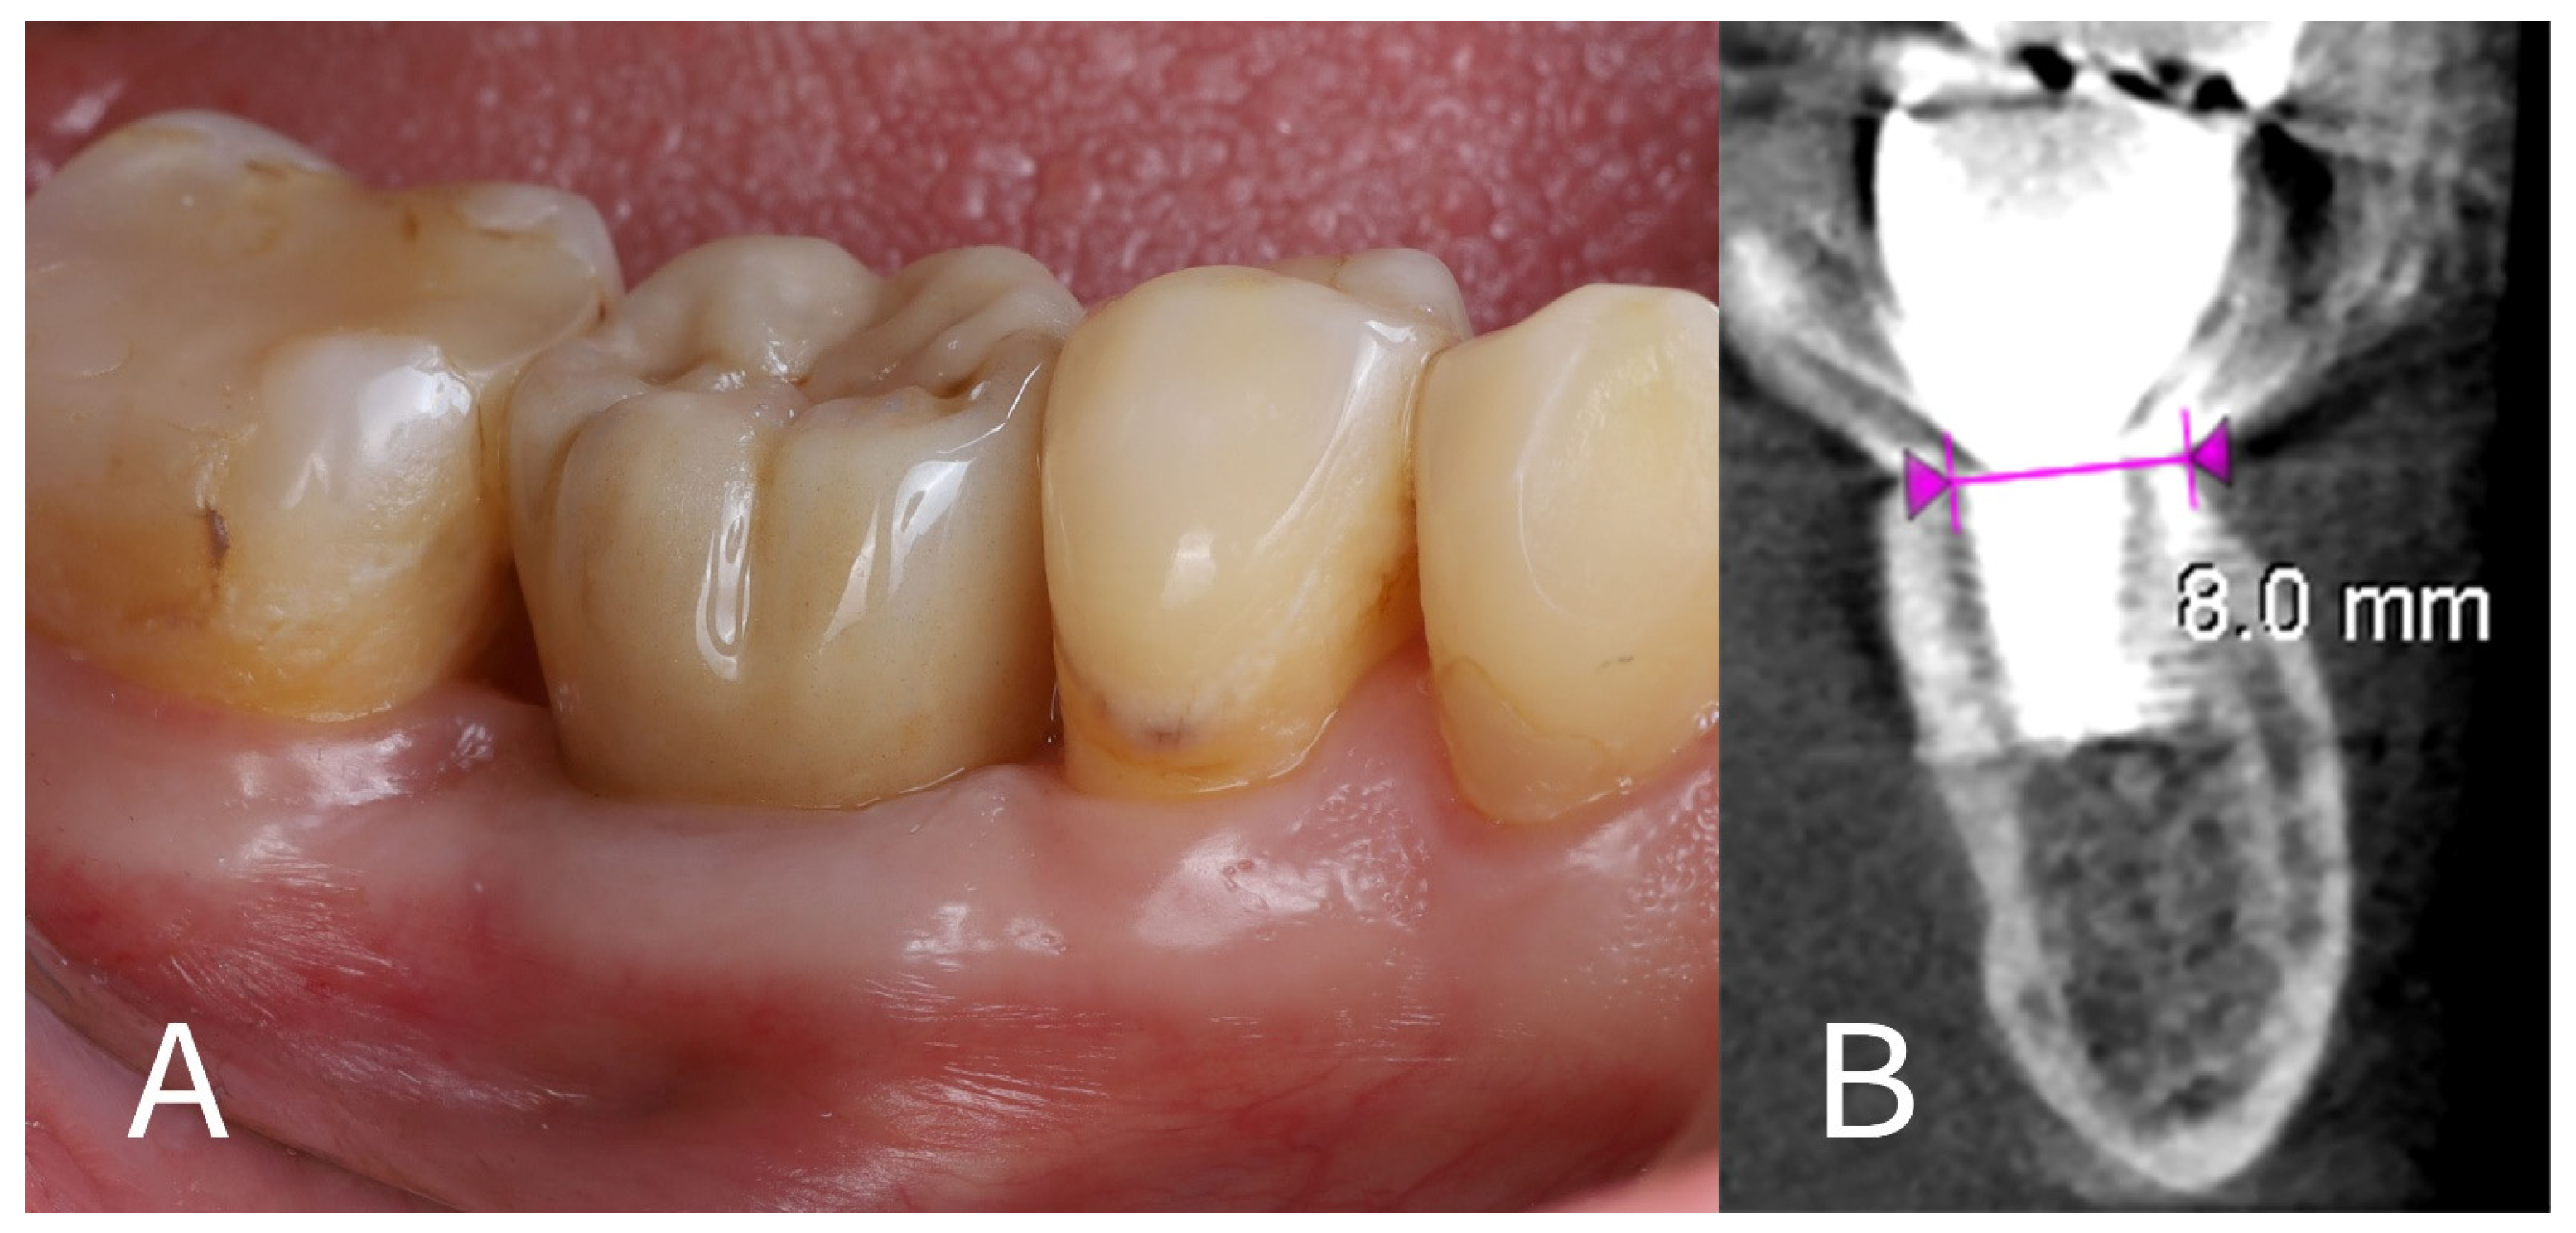

- Immediate post-op imaging: A postoperative CBCT scan was obtained to evaluate the implant position and to measure the alveolar ridge dimensions after implant placement (Figure 6). CBCT confirmed that the implant was accurately centered in the socket.